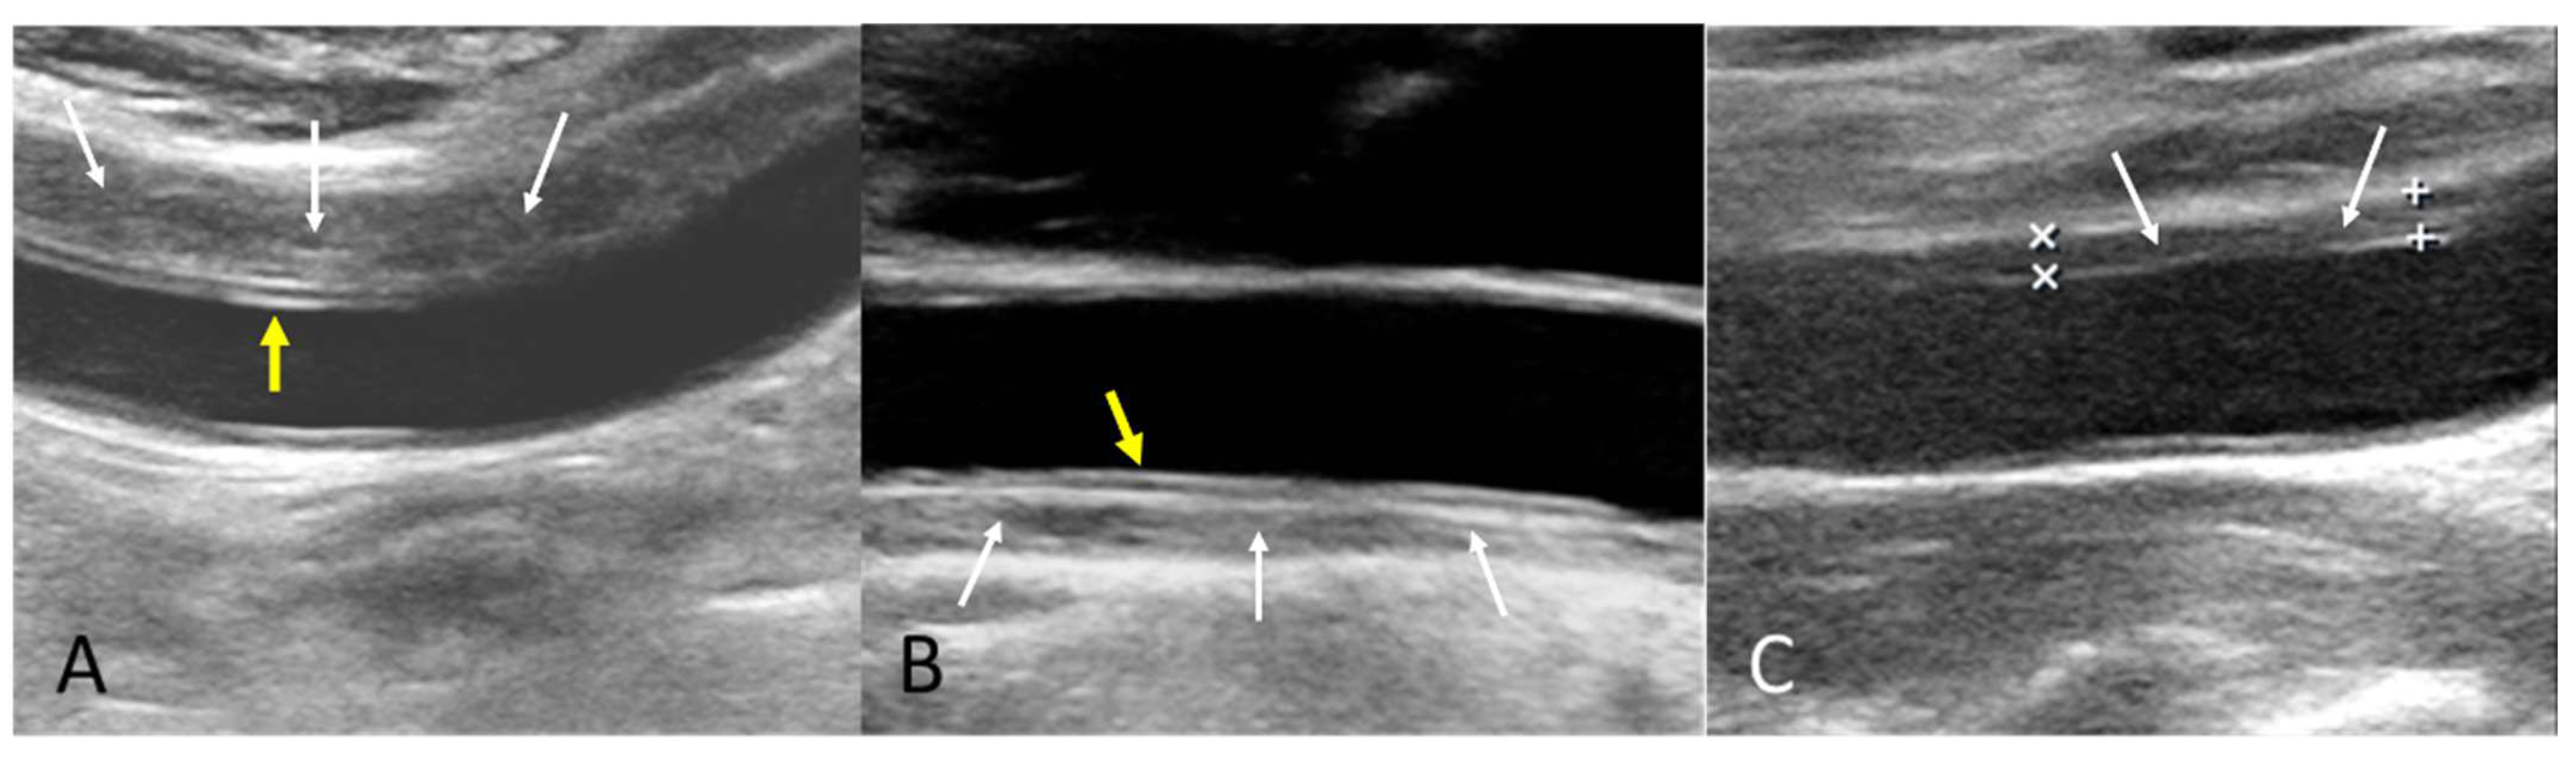

The B-mode findings of the nine CCAs revealed six typical double lumens with intimal flaps (Figure 2) and three intramural thrombi, which are also termed thrombosed false lumen (Figure 3). Supplementary Figures S1 and S2 contain the original ultrasound images. The “train-line” pattern was recognized in three of six intimal flaps and two of three intramural thrombi. The extracranial duplex sonography revealed a “train-line” pattern characterized by a thickened wall displaying hypoechoic properties, where the boundary was composed of closely placed parallel linear reflections. Patient No. 1 corresponds to Figure 2A; patient No. 2 corresponds to Figure 2B; patient No. 3 corresponds to Figure 2C,D; patient No. 4 corresponds to Figure 2E; and patient No. 5 corresponds to Figure 2F. Patient No. 6 corresponds to Figure 3A; patient No. 7 corresponds to Figure 3B; and patient No. 8 corresponds to Figure 3C. Interestingly, patient No. 5 had bilateral CCAD, but the train-line pattern was only on the right side. Figure 2C shows the right CCA with a double lumen and a clearly visible train-line pattern, and Figure 2D displays the left CCA, which also demonstrates a double lumen, but no train-line pattern is observed. Patient No. 8 presented with a hypoechoic intramural thrombus which resembled double lumens, but it was easy to distinguish under the color Doppler imaging.

Figure 3.

Intramural thrombus with train-line pattern (A,B) and without train-line pattern (C). The ultrasound image was obtained using a 4× magnification setting. Yellow arrows indicate the train line. White arrows indicate intramural thrombus. Symbols such as “×” and “+” were generated by the ultrasound machine and used by sonographers to mark ROIs.

The following supporting information can be downloaded at https://www.mdpi.com/article/10.3390/diagnostics15101297/s1, Figure S1: Original B-mode ultrasound images of CCAD patients with double lumen and intimal flap with train-line pattern (A–C) and without train-line pattern (D–F); Figure S2: Original B-mode ultrasound images of CCAD patients with intramural thrombus with train-line pattern (A,B) or without train-line pattern (C). Table S1: Doppler waveforms of patients No. 1 to No. 8.